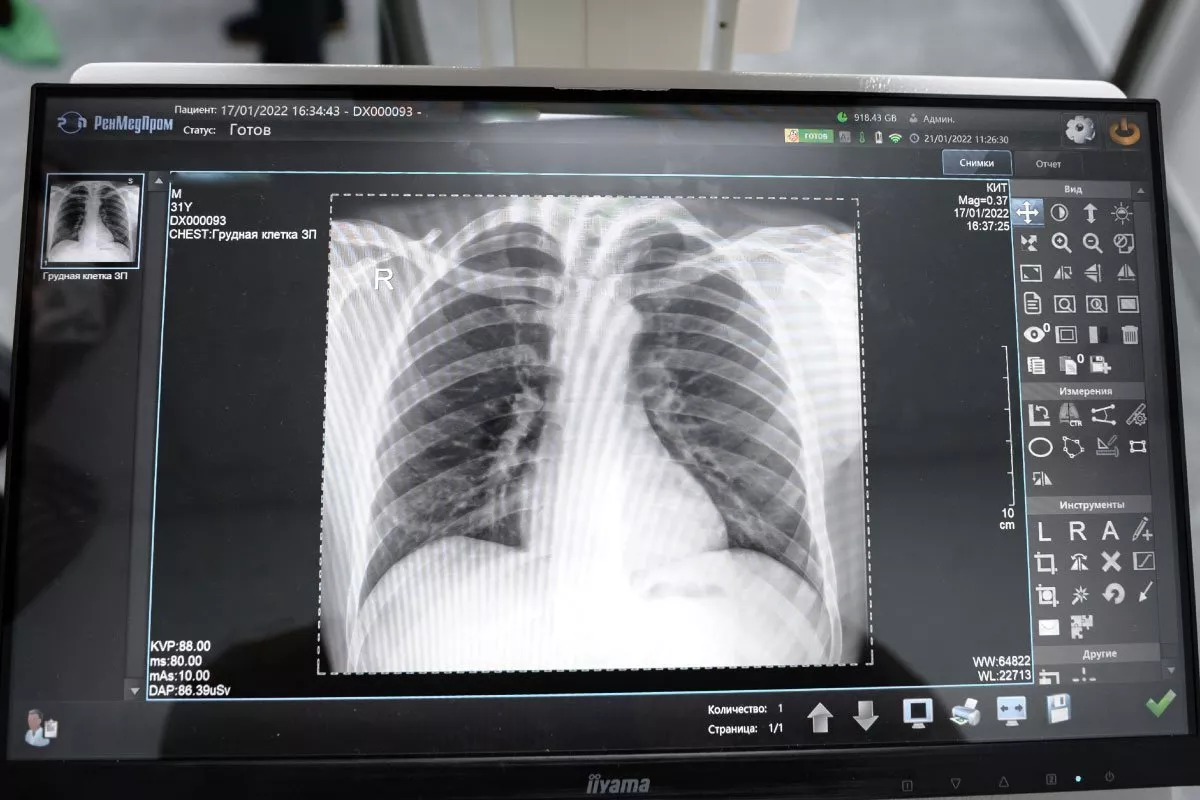

Рентген-аппарат «Дельта» — современная цифровая рентгенографическая система, предназначенная для быстрой и точной диагностики заболеваний костей, суставов и внутренних органов.

Аппарат позволяет получать высококачественные цифровые изображения сразу после экспозиции, что помогает врачу оперативно оценить состояние пациента и принять решение о дальнейшем лечении.

Рентген-аппарат «Дельта» — современная диагностическая система, предназначенная для проведения рентгенографических исследований костей, суставов, органов грудной клетки и других анатомических областей.

Аппарат использует цифровые технологии регистрации изображений, что обеспечивает высокую точность диагностики и позволяет получать качественные рентгеновские снимки практически сразу после проведения исследования.

• Высокое качество цифрового изображения — снимок формируется на экране сразу после исследования.

3. Получение изображения. Снимок отображается на мониторе врача.